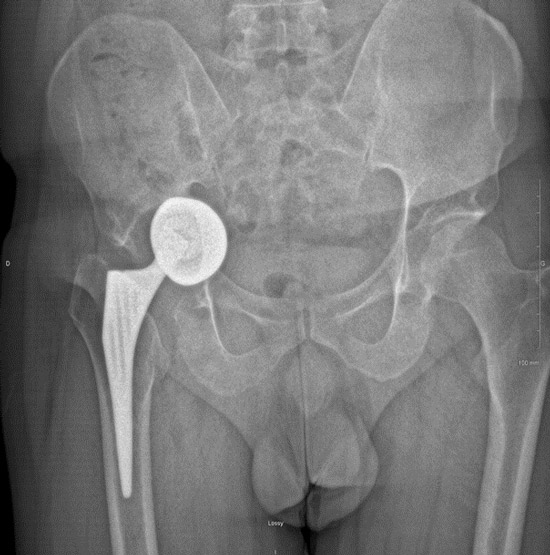

> 2 years imagery

Postoperative imagery

Function / Clinical examination

• All activities without limitation, including running

• « Forgotten hip »

• 110/20/30/45